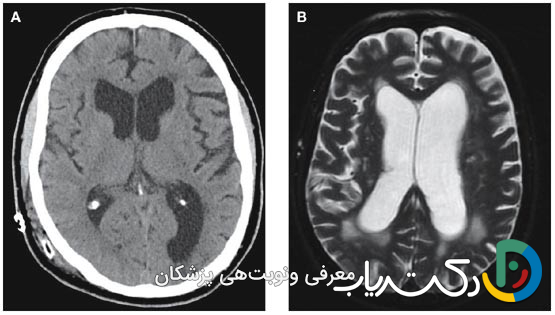

- تشخیص قطعی: تشخیص دقیق یک فرآیند چندمرحلهای است که با معاینه کامل عصبی آغاز شده و با روشهای تصویربرداری پیشرفته مغز مانند MRI (استاندارد طلایی برای مشاهده جزئیات) و CT اسکن (برای ارزیابی سریع و اورژانسی) تأیید میشود.

- اسکن توموگرافی کامپیوتری: سیتی اسکن با استفاده از اشعه ایکس، تصاویر مقطعی و سریع از مغز ایجاد میکند. این روش برای تشخیصهای اورژانسی (مانند پس از یک آسیب شدید به سر) یا برای ارزیابی سریع اندازه بطنها بسیار مفید است. سیتی اسکن بهوضوح میتواند بزرگ شدن بطنها و وجود خونریزی حاد را نشان دهد.

- تصویربرداری رزونانس مغناطیسی (MRI): امآرآی بهعنوان استاندارد طلایی برای تشخیص و ارزیابی کامل هیدروسفالی شناخته میشود. این روش بدون استفاده از اشعه ایکس، با استفاده از امواج رادیویی و یک میدان مغناطیسی قوی، تصاویر بسیار دقیق و با جزئیات بالا از ساختارهای نرم مغز ایجاد میکند. MRI نه تنها بزرگ شدن بطنها را با دقت فوقالعاده نشان میدهد، بلکه میتواند علت زمینهای مانند تومور، کیست، التهاب یا ناهنجاریهای ساختاری را نیز شناسایی کند. سکانسهای خاصی از MRI (مانند CINE-MRI) حتی میتوانند جریان و سرعت حرکت CSF را در مغز به تصویر بکشند و به تشخیص نوع انسدادی از ارتباطی کمک کنند.